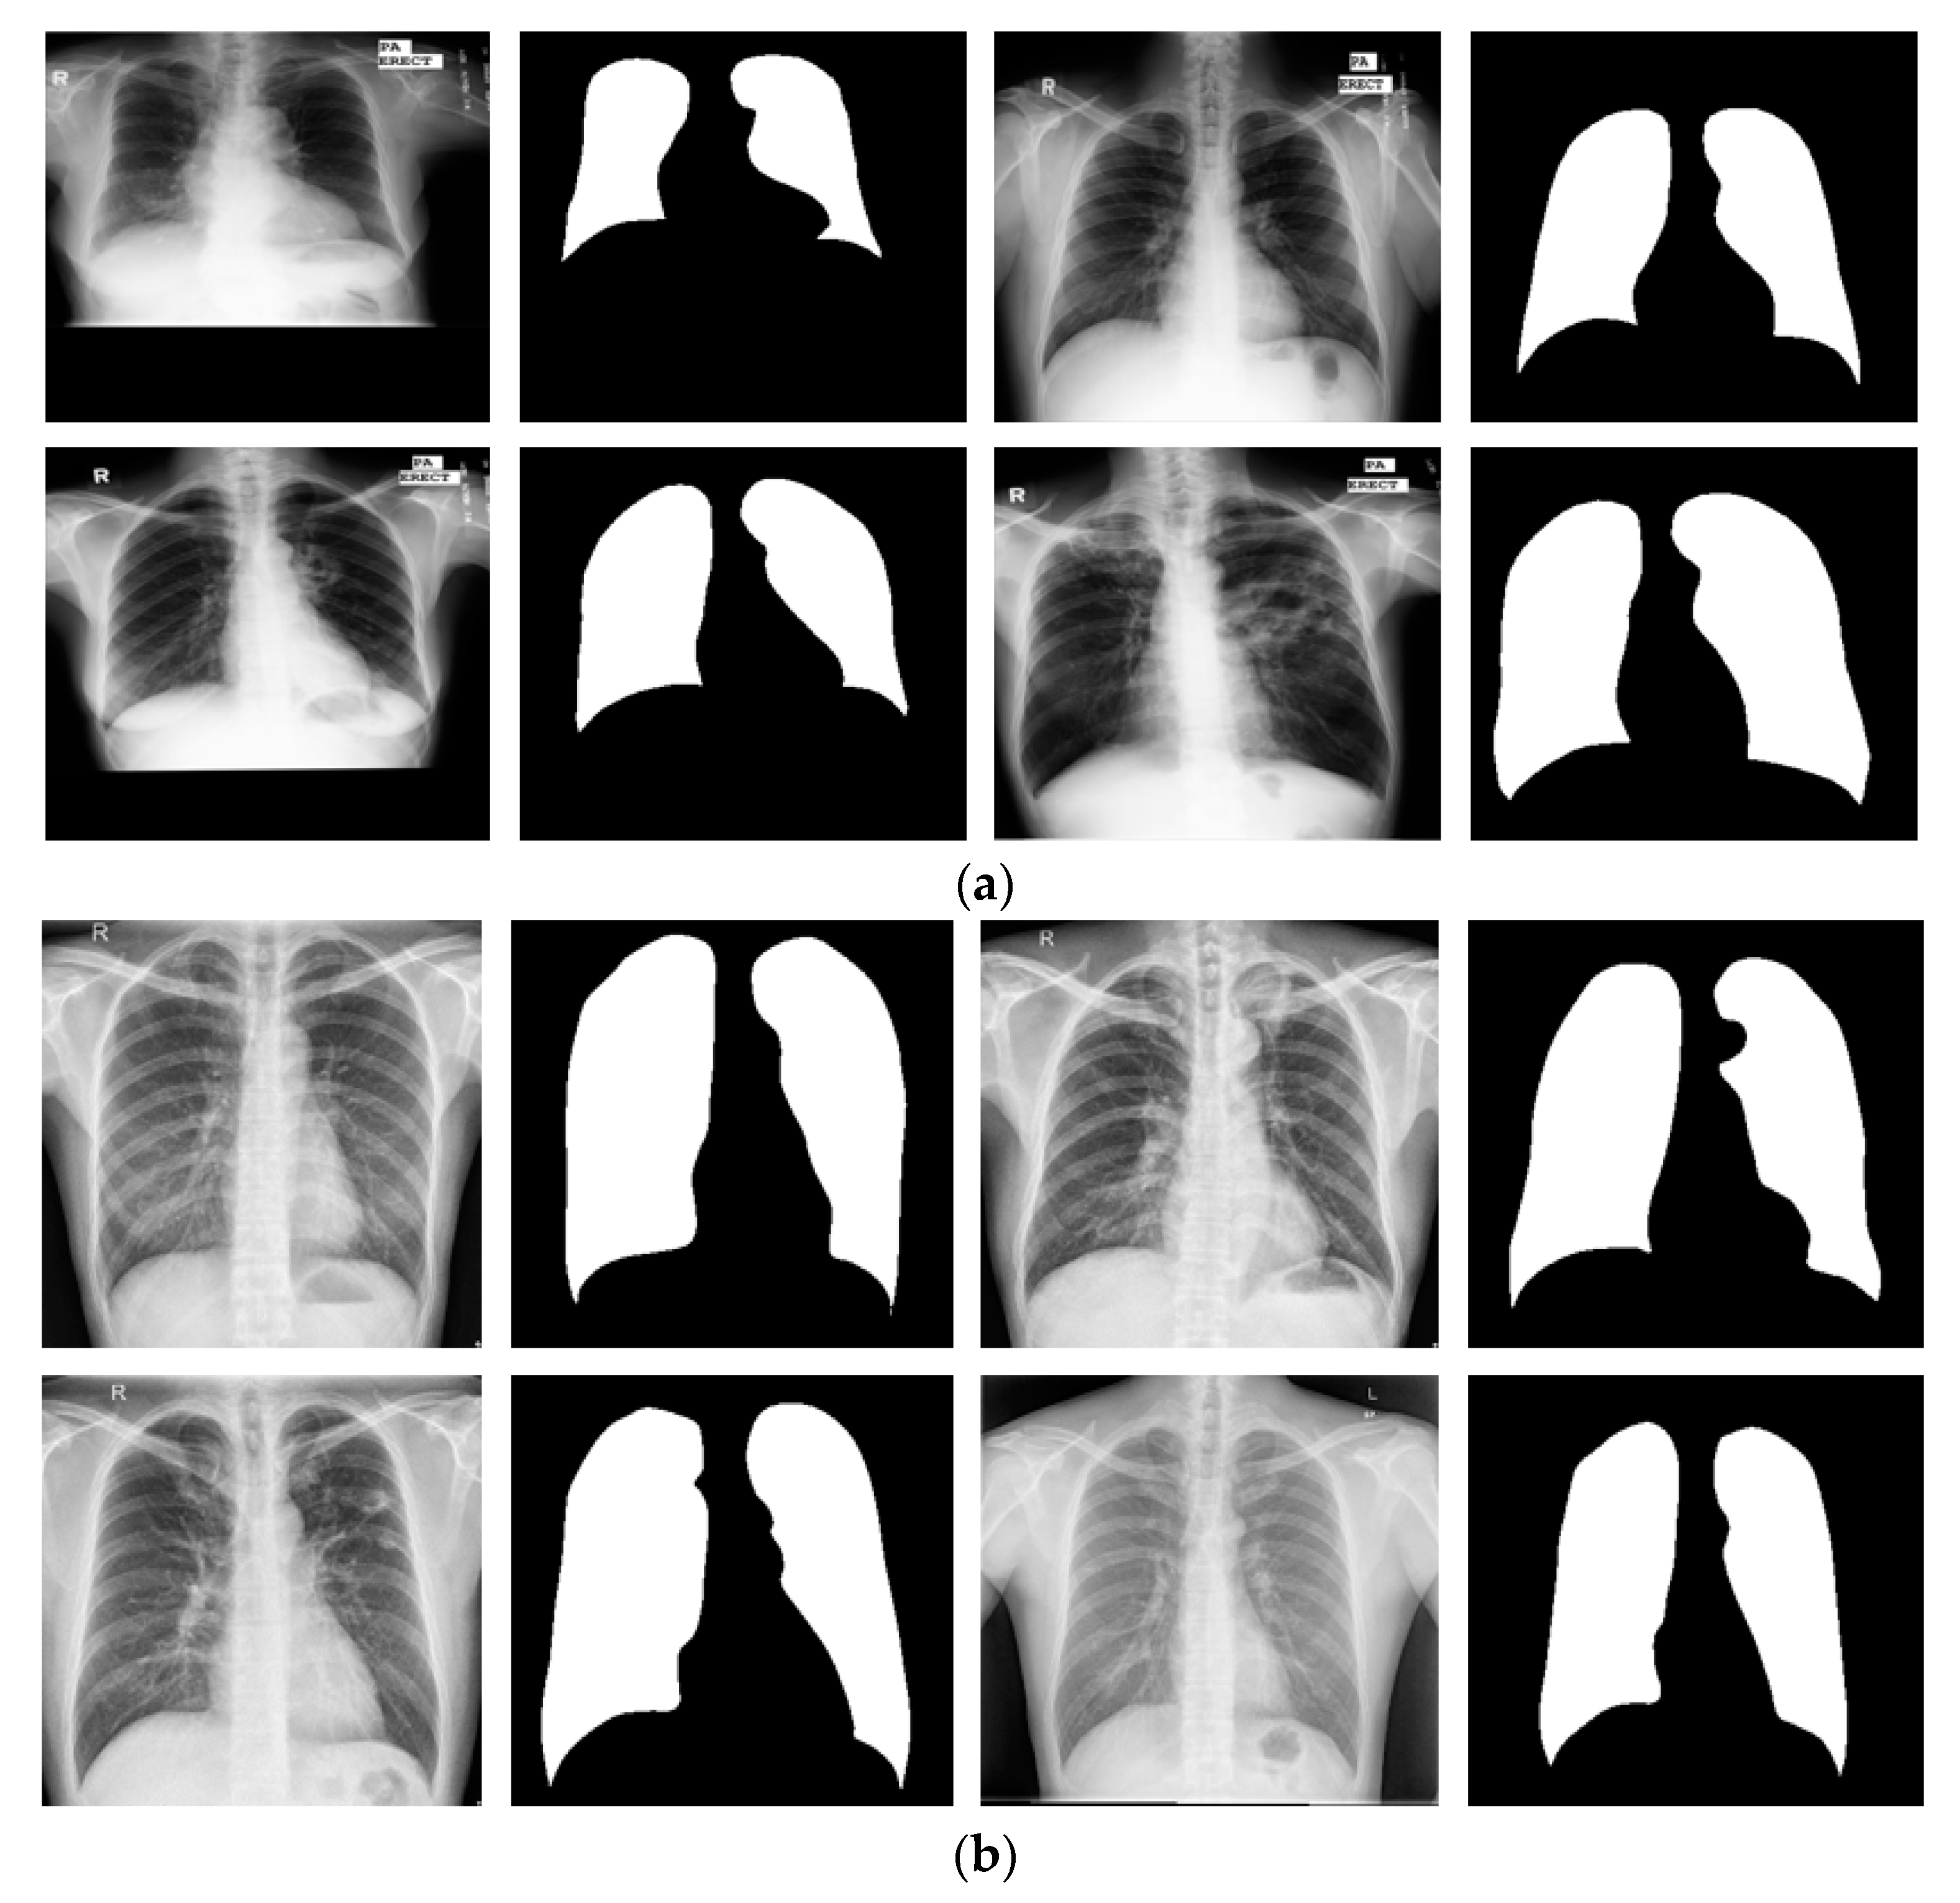

3.4.4. Lung Segmentation with Other Open Datasets Using X-RayNet